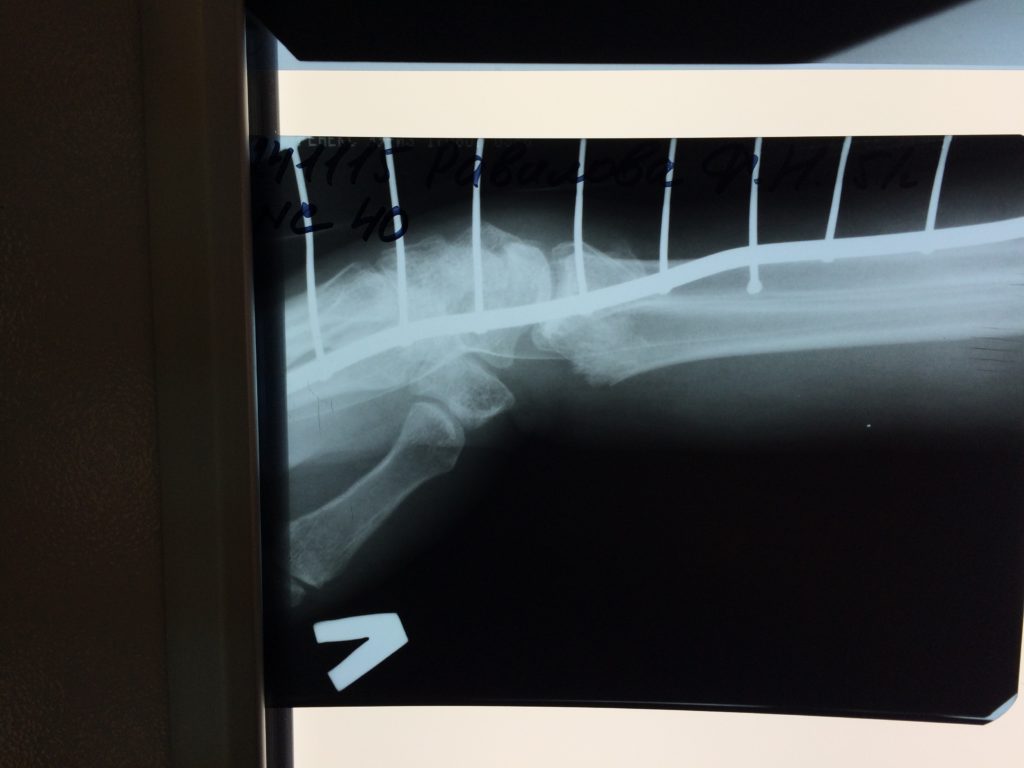

Операция - открытая репозиция, остеосинтез лучевой кости пластиной с костной ксенопластикой материалом "Остеоматрикс". На контрольных снимках в три месяца имеется консолидация перелома, миграции фиксатора нет, имеется остеоинтеграция ксенопластического материала.

Отдаленные результаты через 3 (три) месяца: